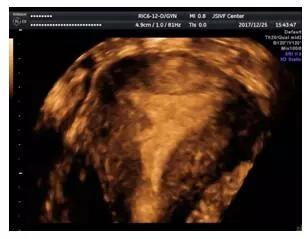

三维超声成像的右侧宫壁粘连

适时三维图像还具有自由旋转功能,可以对粘连的部位进一步明确及测量病变面积。在冠状切面,可以显示宫腔及内膜的整体形态,正常情况下是倒三角形,左右对称,双侧宫角锐利,内膜及肌层分界清晰规整,内膜回声均匀。当发生宫腔粘连时,中央性粘连表现为内膜的缺损,回声不均匀等,周围性粘连则可能变现为倒三角形结构的破坏,宫底部或双侧壁的不对称,宫角圆顿,宫腔缩窄,内膜及基层分界不清晰,不规整等。

三维超声对于诊断中重度宫腔粘连的准确性达90%以上,它具有无创,方便,快捷,高效的优点,与传统的子宫输卵管造影比较,经阴道三维超声检查具有更好的实用价值,已得到国内外该学术研究领域学者的一致认可。